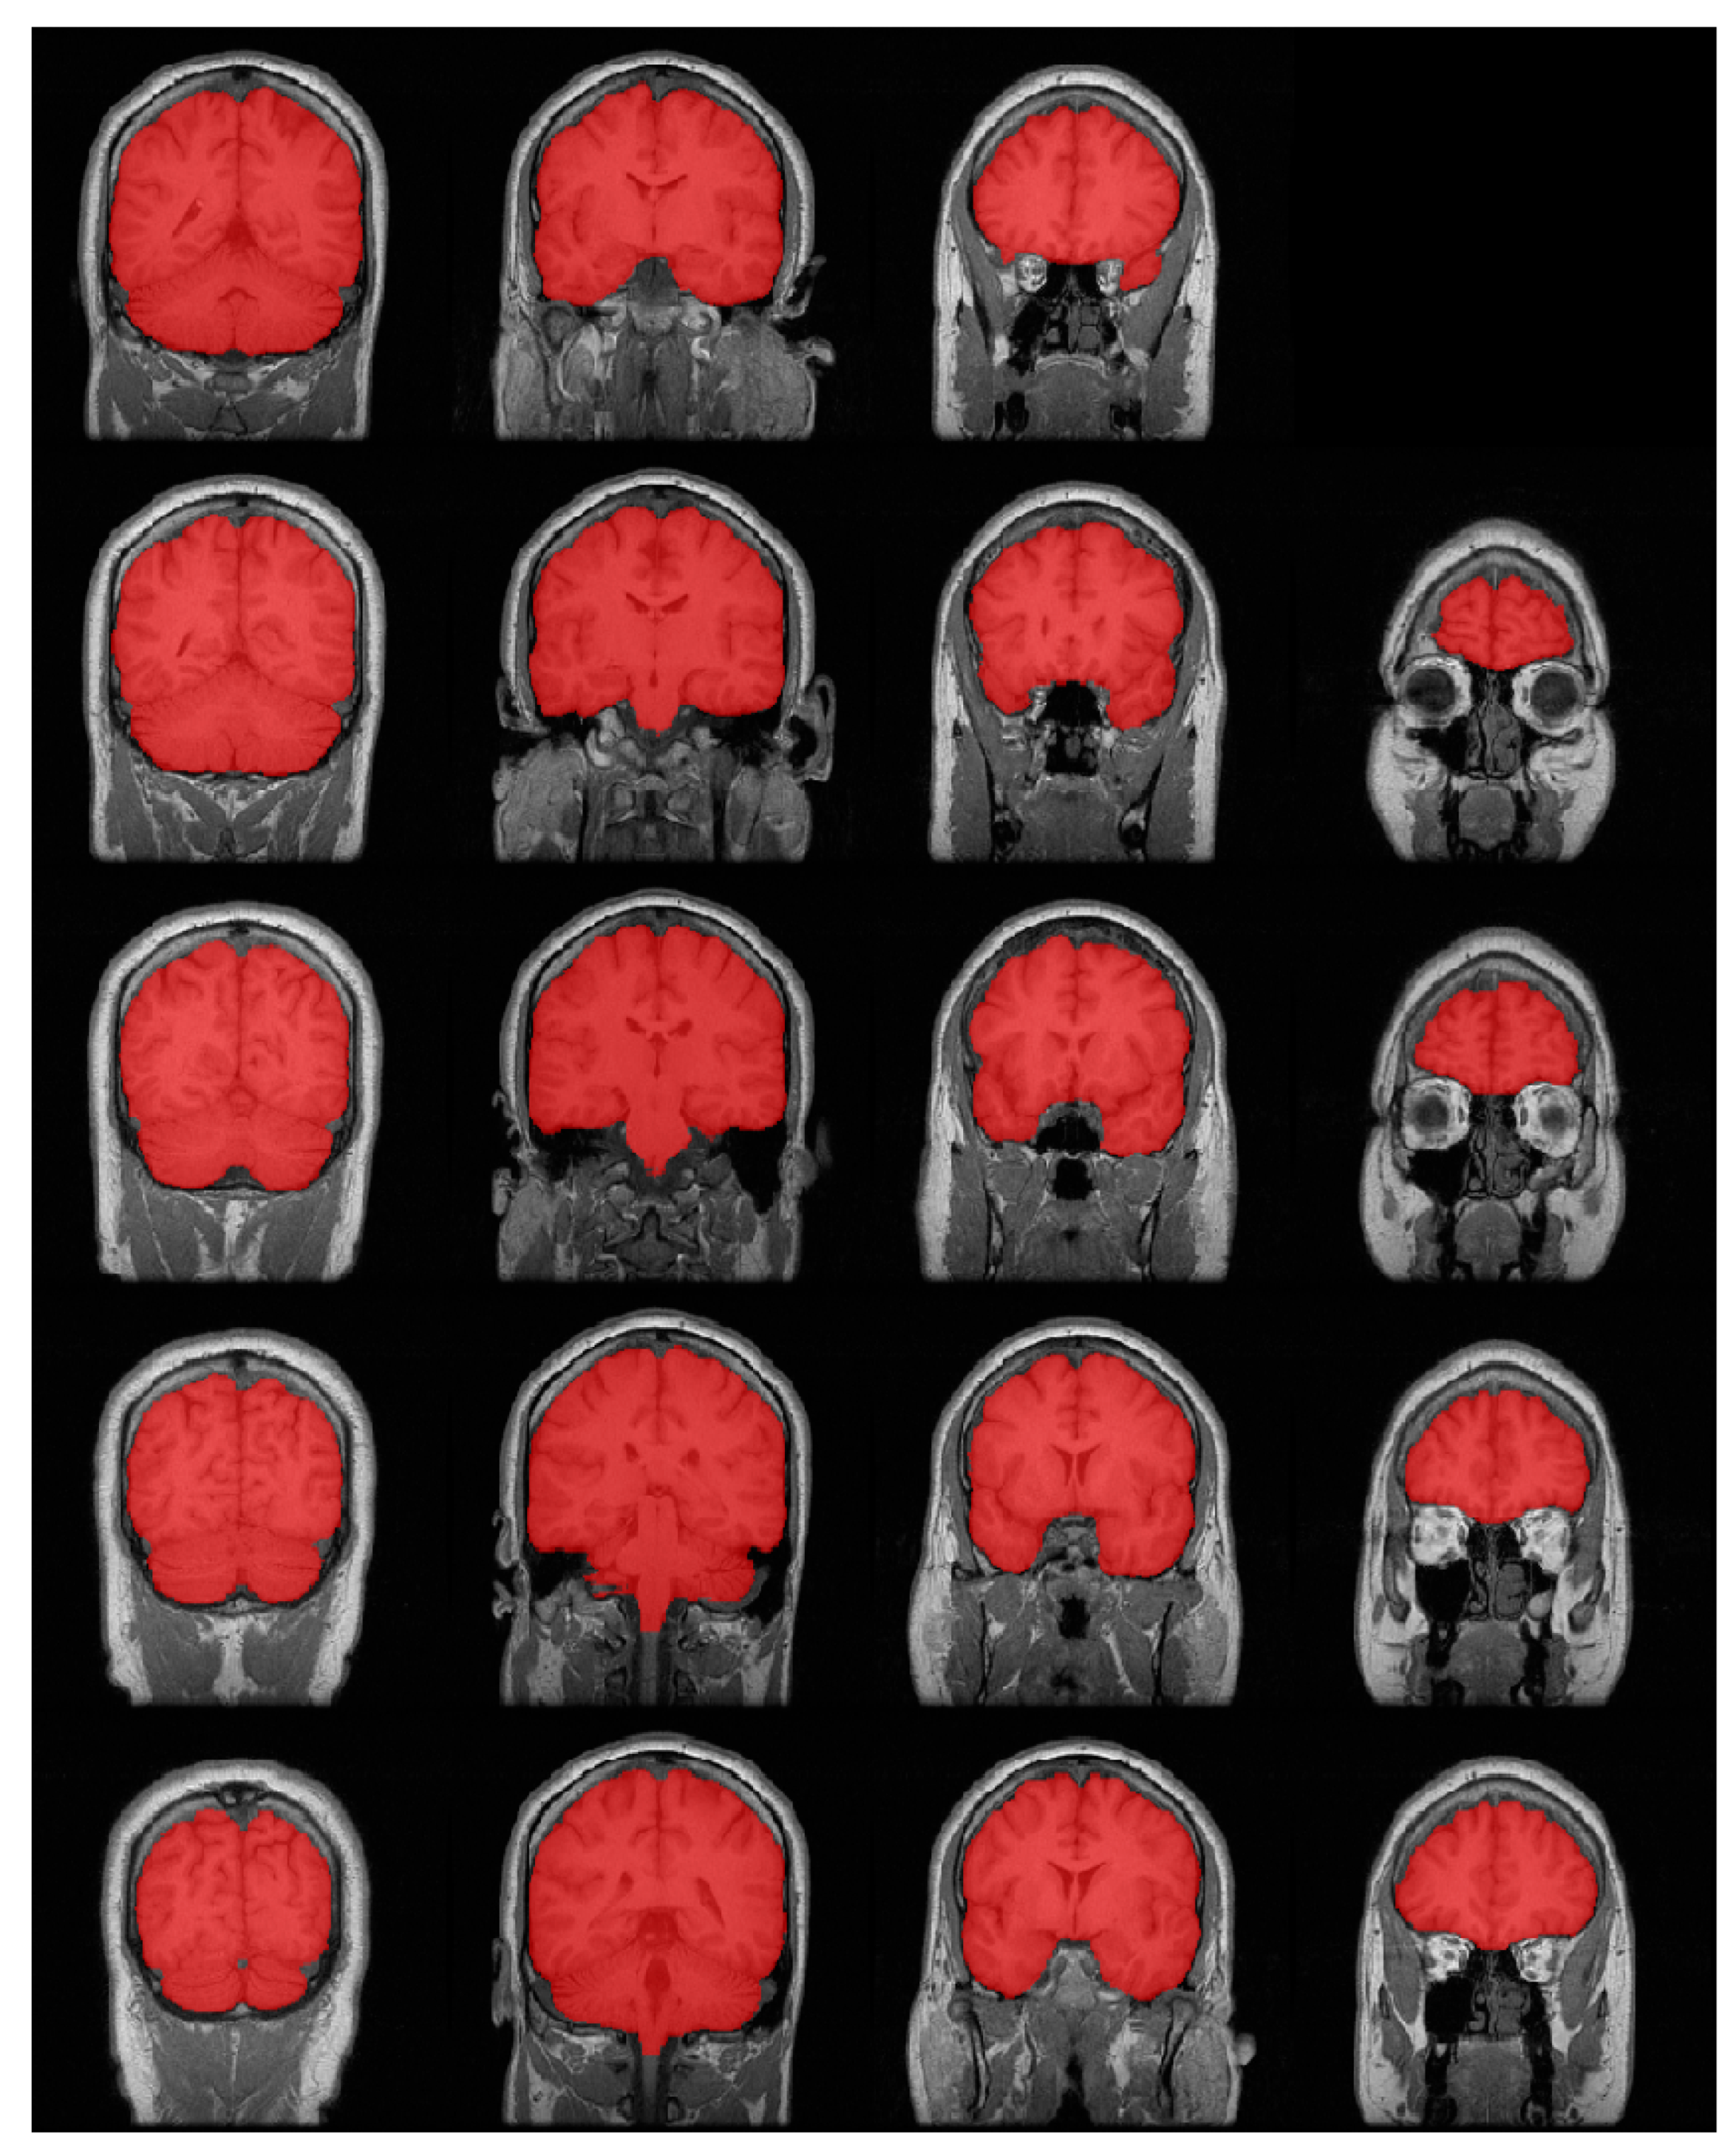

3.2. Results